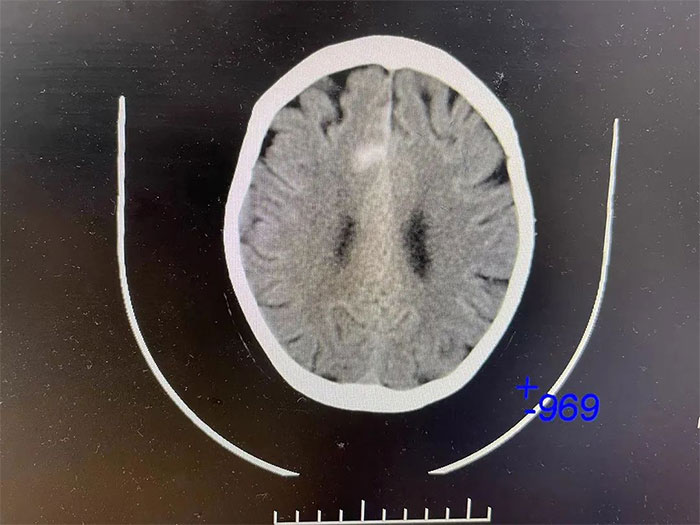

▲ 入院检查颅内仍有出血活动

更令人不安的是,CT检查显示,吴阿姨右侧大脑顶叶出血灶较前变化不明显,提示仍有出血活动,若不及时进行干预,随时都有“决堤”的可能,不仅影响神经功能恢复,病情还可能因之进一步恶化,甚至危及生命。